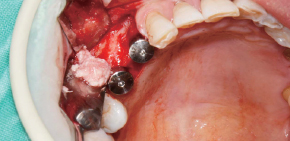

A Clinical Case using Ø3.5/4.0 Harvesting Drill

by Dr. Soohong Kim, DDS, Ph.D

-

Drilling at 300 rpm with irrigation was carried out after marking implant and harvesting position.

The Silicone Shield was brought into close contact with various types of bone level and prevented bone chip loss.

The amount of bone taken was easily ascertained, through the transparent Silicone Shield.

The bone was transferred to bone dish after disassembling the Silicone Shield and Stopper.

The amount of the bone was much more than expected.

After the implant placement, healing abutments were connected and carried out GBR in the defected area.